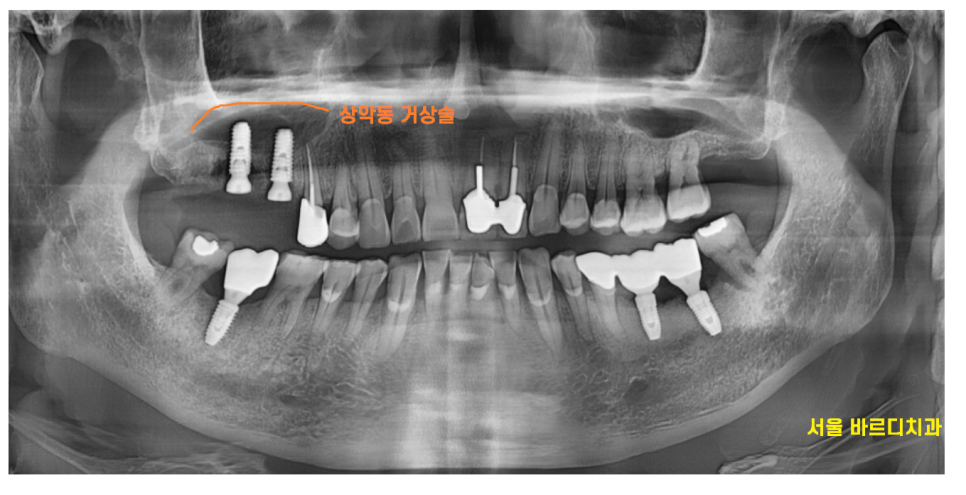

x-ray를 찍어보니

잇몸이 전반적으로 안좋으셨습니다.

그 중에서도 유독~~

눈에 보이는 한 부분이 있네요.

23.07.04

오른쪽 위에 치아가 뿌리 모양이 이상해보였습니다.

역시나 작은 사진을 통하여

검사를 해보니

뼈가 많이 녹았네요.

염증으로 인하여 잇몸 뼈가 녹고

그로 인하여 잇몸이 들뜨니

치아 솟음 느낌을 받으신거죠.

23.08.22

치아 솟음으로 문제를 일으킨

치아 두개를 뽑고

부족한 뼈를 이식하였습니다.

단단하게 땅을 만든 뒤

상일동역 임플란트를 식립